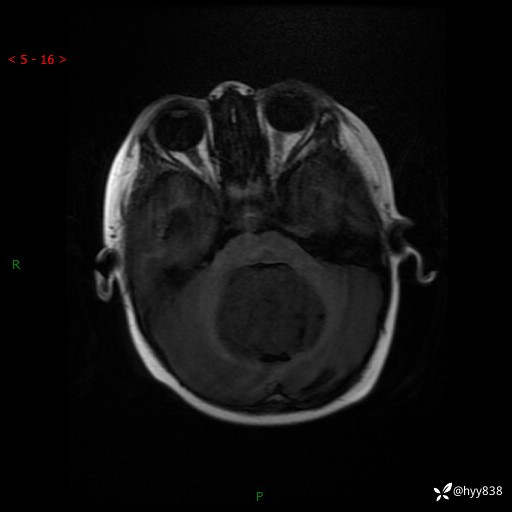

颅脑CT平扫

颅脑MRI平扫+增强

三脑室、四脑室多发病变,如何分析?